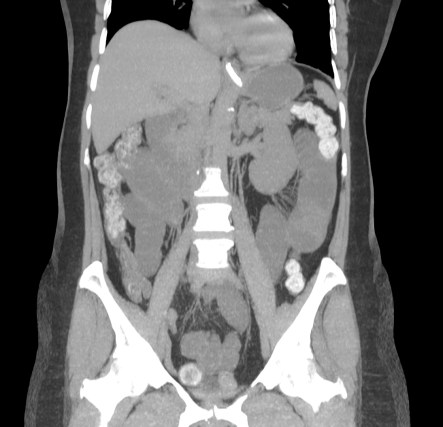

Se realiza placa de abdomen y TC en vacío y fase portal.

El cuadro oclusivo está producido por una litiasis biliar que ha pasado de la vesícula al intestino a través de una fístula con el duodeno y que llegó hasta el recto por una insuficiencia de la válvula ileocecal. Así, se produjo una dilatación generalizada de asas, principalmente de las del intestino grueso, que finalmente derivó en isquemia intestinal.

- Dilatación por obstrucción de asas de delgado.

- Aerobilia.

- Litiasis (2 – 3 cm aprox). Hay que tener cuidado ya que muchas litiasis no están calcificadas y su densidad puede ser similar al contenido del intestino. Pueden ser multiples, por tanto hay que poner atención para que no pasen desapercibidas y evitar las recidivas.

- Fistulas (normalmente entre vesícula y duodeno)